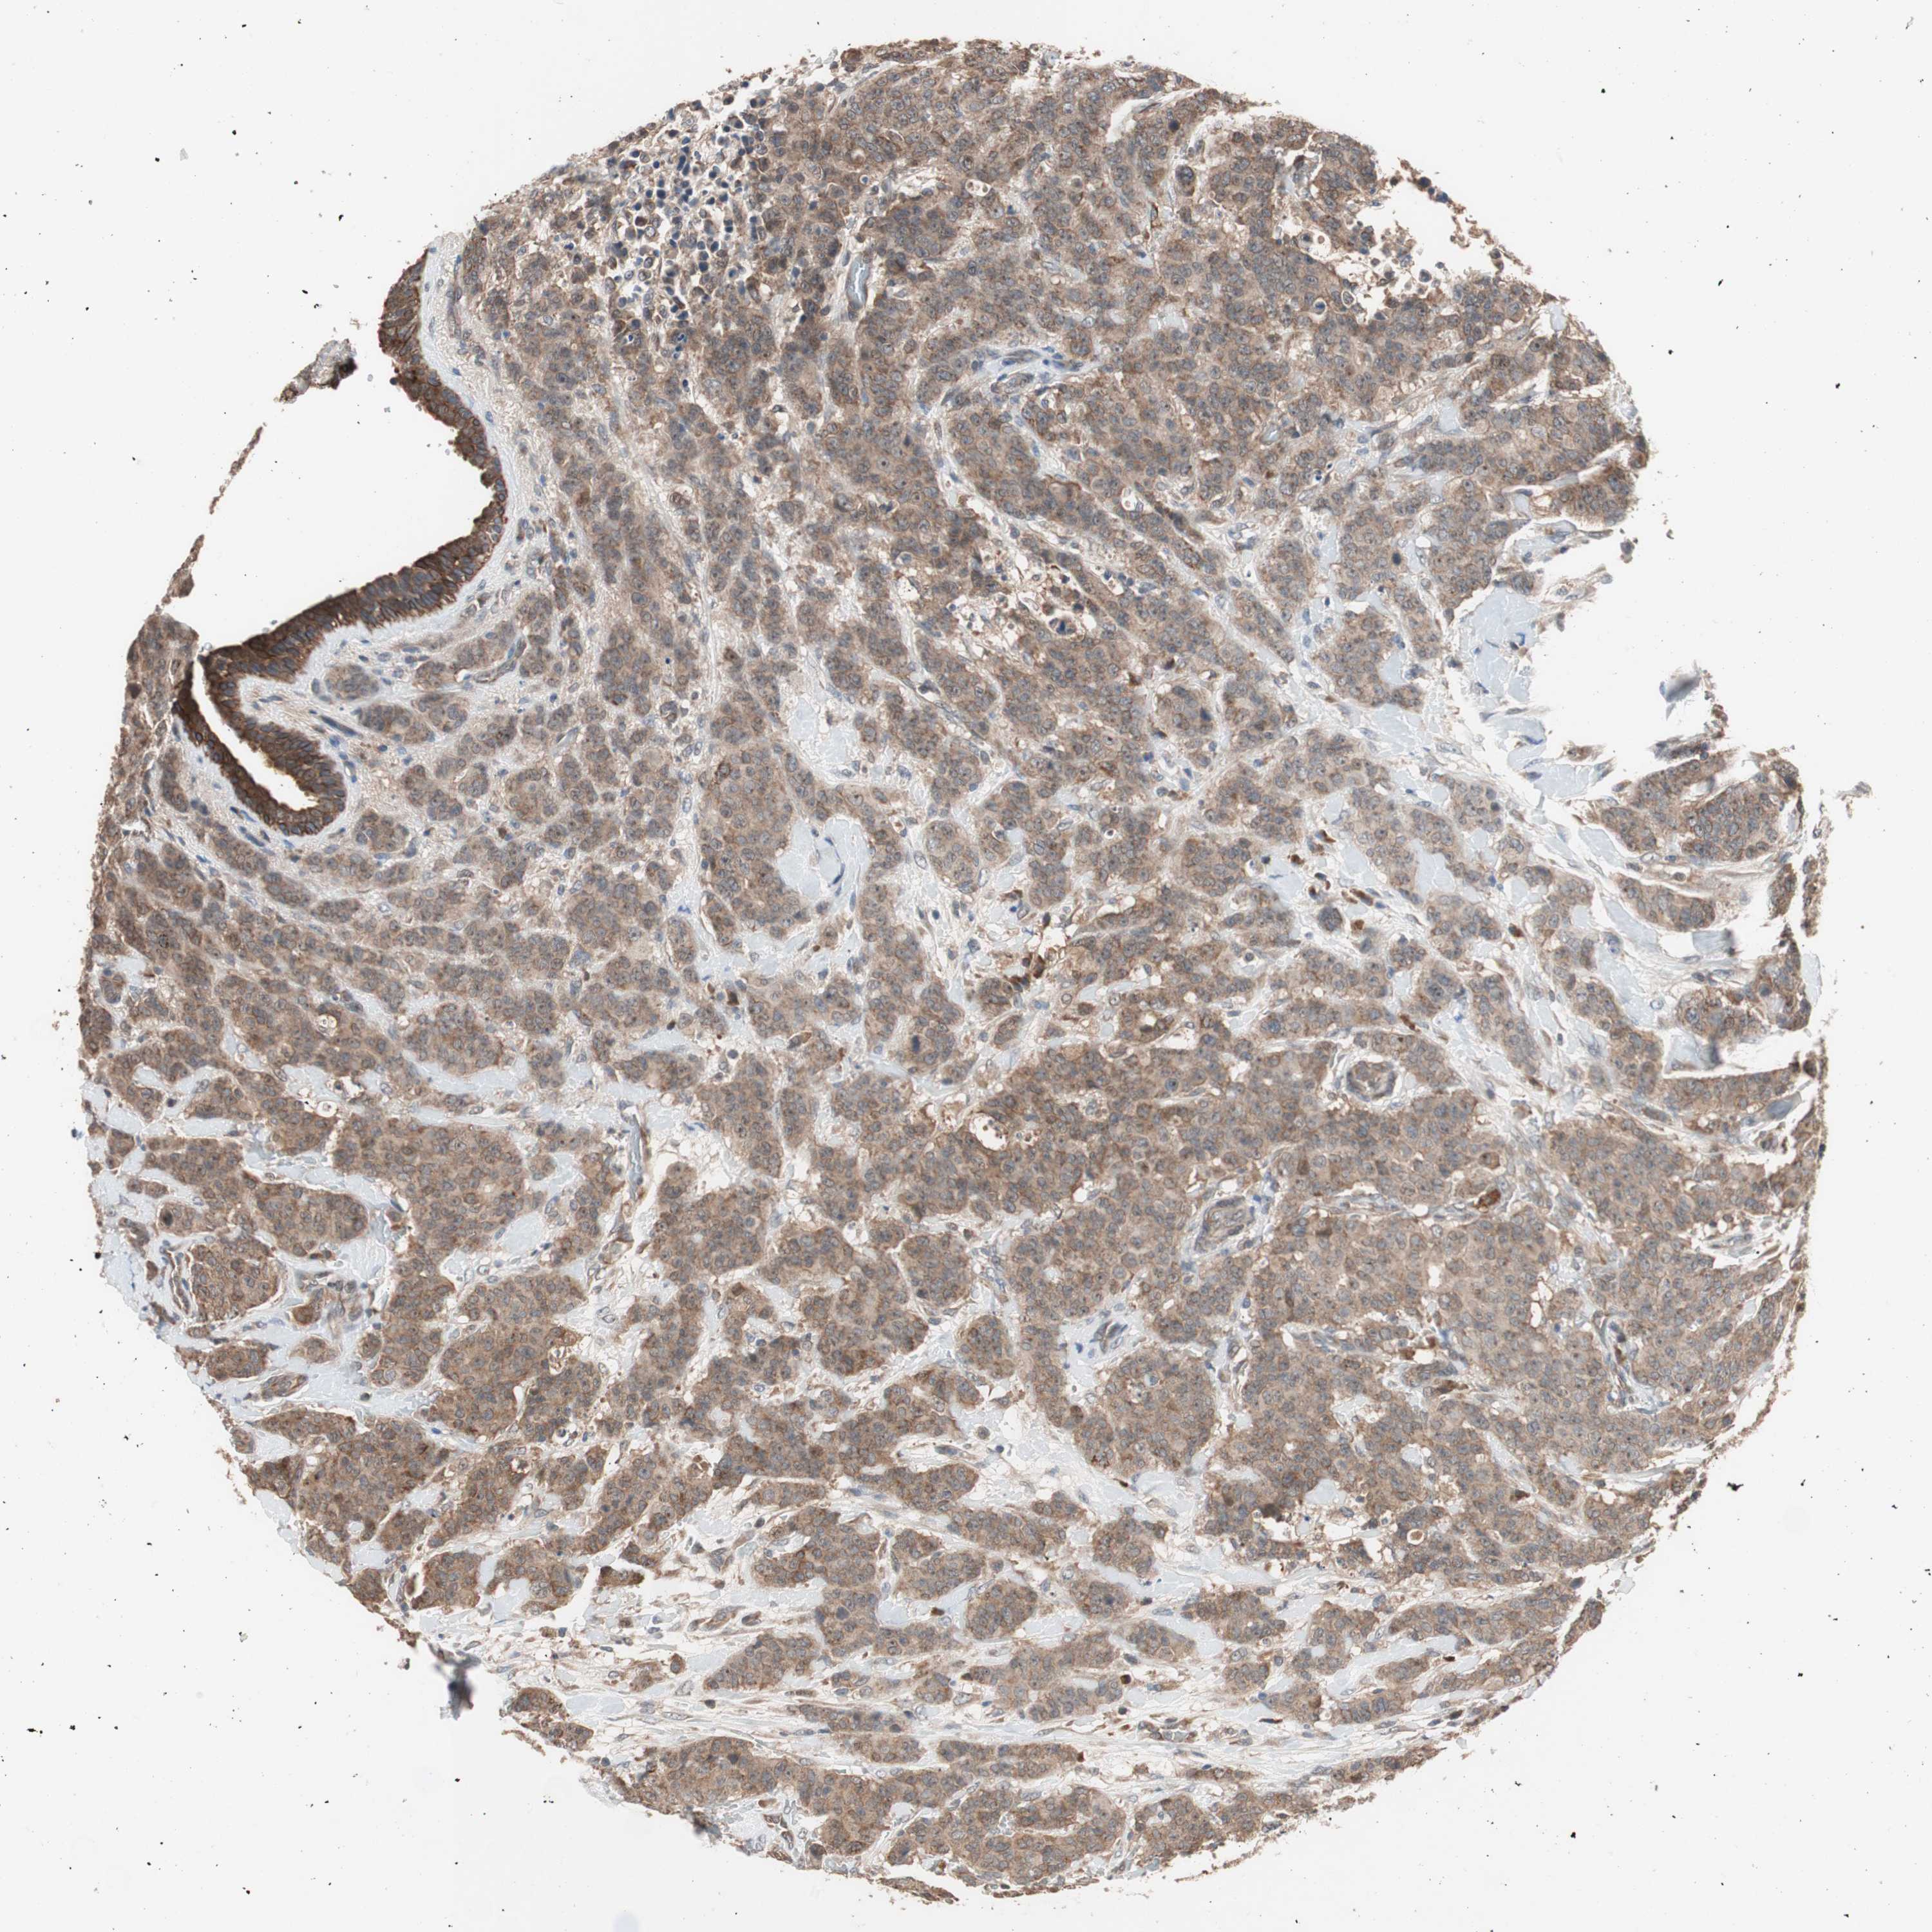

CANCER BREAST CANCER Show tissue menu

Breast cancer

Human cancer